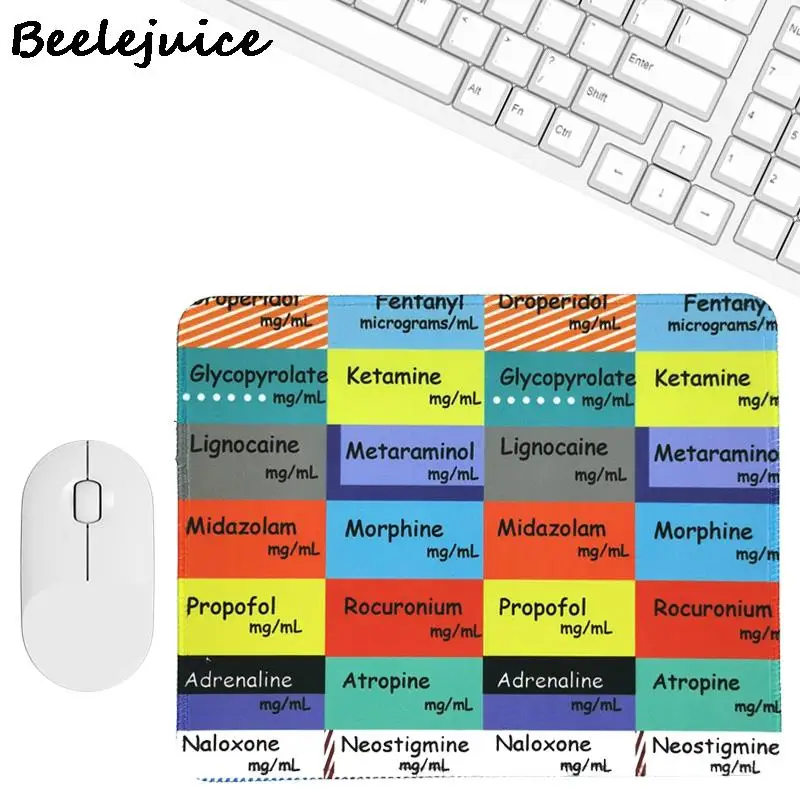

Medical Pattern Silicone Mouse Pad Nature Nordic Style Mouse Pad for Gaming Laptop Desk Pad Mouse Pad Wrist Rest Office Desk Pad